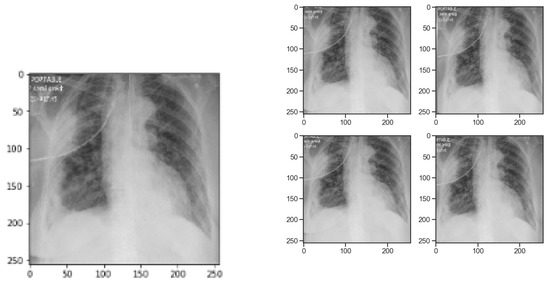

Image Augmentation with Keras ImageDataGenerator Class